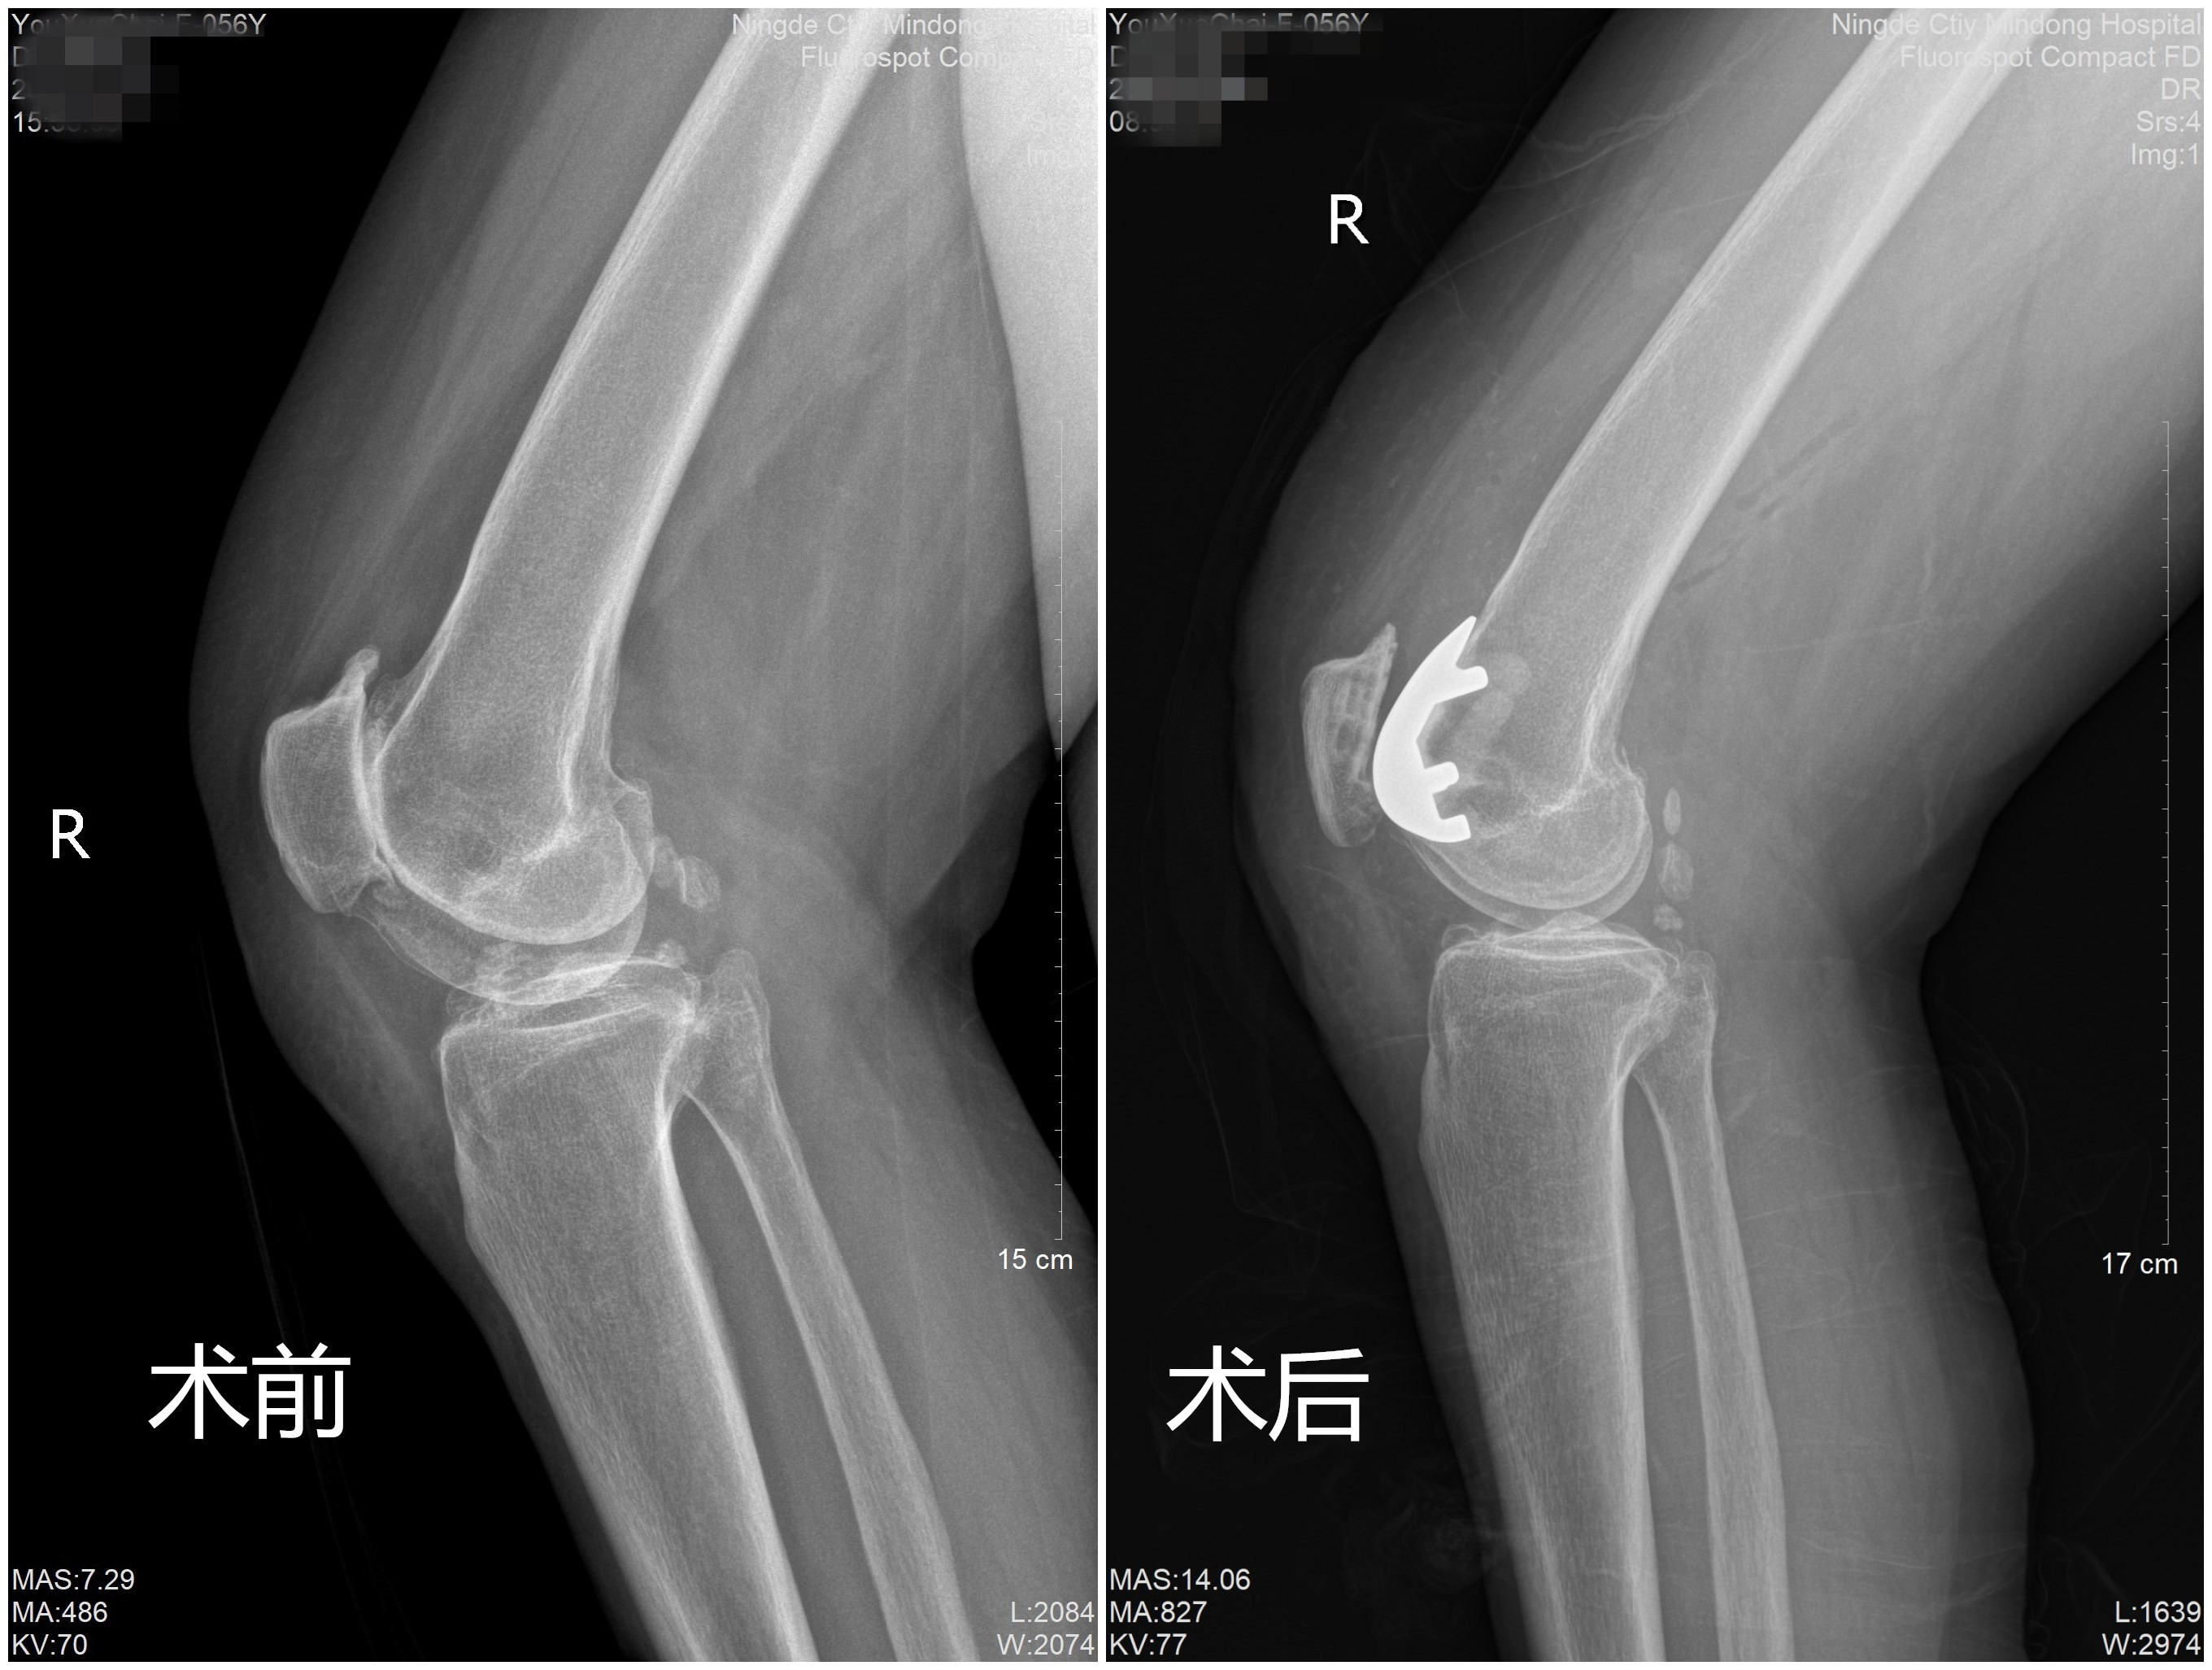

福建卫生健康新闻网讯(通讯员 王体惠 文/图)近日,家住霞浦县的54岁王阿姨,长期右侧膝关节疼痛,尤其是上下楼梯困难,严重影响日常生活。慕名求诊于闽东医院关节外科与运动医学科,在该科王旭主任医师的带领下,成功为王阿姨施行宁德市首例人工髌股关节置换术,为患者拔“病根”让“旧”关节重焕新活力,帮助患者恢复关节功能,提高生活质量。

患者入院后,王旭主任医师、吴锦清主任医师、王体惠副主任医师详细询问她的病史,仔细检查患者膝关节,指出其主要病症在髌股关节,而胫股关节相对比较完好,经X线摄片及核磁共振检查后确诊为右侧髌股关节炎。认为患者有行人工髌股关节置换指征,经征得患者及其家属同意和做好充分术前准备,为患者行人工髌股关节置换术,手术仅用一个多小时,术中出血少,术后患者膝关节肿胀轻,术后第二天下地行走,术后五天康复出院。 王旭介绍说道,人工髌股关节置换术主要适用于单纯性髌股关节炎、创伤性髌股关节炎、髌骨软化症及股骨滑车发育不良等情况引起的髌股关节活动性疼痛及活动受限,主要人群为40-65岁的中老年患者,女性居多。人工髌股关节置换术为膝关节单间室置换术,相比人工全膝关节置换术,手术创伤小、出血少、术后恢复快,同时保留膝关节正常生理运动学特征及本体感觉,术后膝功能更加理想。 髌股关节炎需要引起中老年人重视,如果髌股关节炎得不到及时的治疗,会严重影响患者的日常生活。王旭提醒说道,预防髌股关节炎,控制体重是关键。过度肥胖会让膝关节承受更大的压力、会让膝关节退化加速。同时,运动要合理,错误锻炼会加重膝关节的退变,爬山、半蹲位等不适合膝骨关节炎患者。平时要注意对关节的保护,如经常蹲下或跪下取物、坐矮凳子、下跪擦地板都会增加髌股关节的受力和摩擦,伤害关节。 随着医学的不断进步,医疗技术的不断发展,很多关节疾病都能得到很好的治疗,取得相对满意的疗效,提高患者的生活质量。单间室膝关节置换手术是微创化人工关节置换手术,术后恢复更快、住院时间更短。闽东医院关节外科与运动医学科在王旭的带领下,精益求精,追求卓越,用自己的实际行动诠释医者初心和使命,为闽东人民的“关节”健康筑起了坚强保障。 |